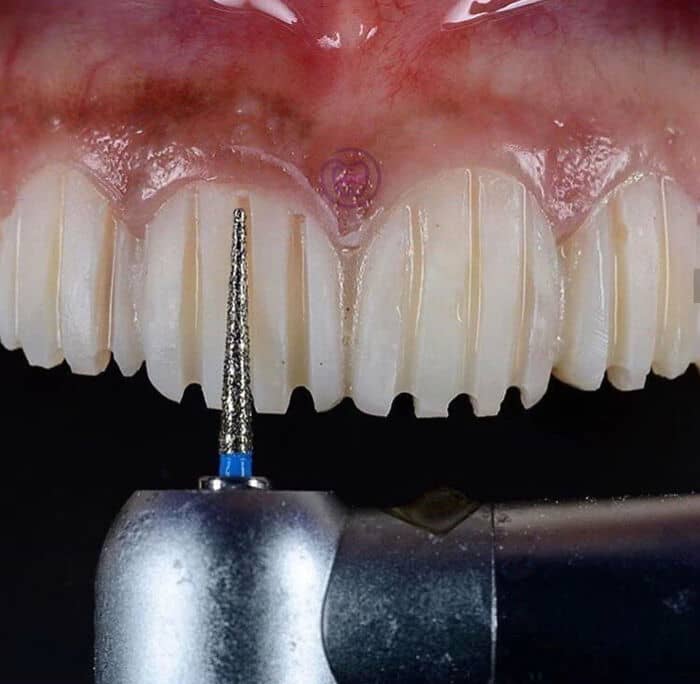

#79 Veneers Preparation